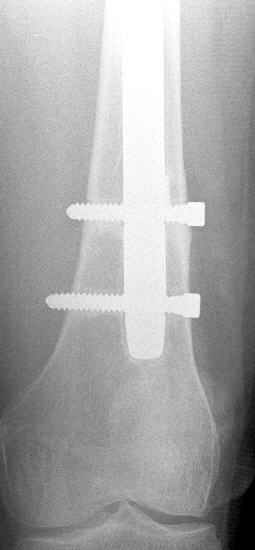

May I have some advice on the following case? Middle aged woman, No chronic medical problems, +tobacco use - but she promises she's going to quit! Original MVC in late 1990's, initial rod failed, and 2 subsequent exchanges failed (most recently shown in attached jpgs.)

Most recent one (6/2002) was apparently an open nailing to remove last broken nail, but no grafting was performed in conjunction. Now sent to me with broken 14mm R/T nail in place.WBC, Hgb, Chemistries normal.ESR 34CRP 4.2No other apparent locus of infection.I was considering a staged approach - removing nail and screws and obtaining cultures.If negative, proceed with exchange nailing with open grafting +/- BMP, But how best to deal with that pedestal distally and avoid anterior breech near patella? If positive cultures, what would be best option?Thanks. Tom Schaller Kalamazoo, MI.

In my opinion, there is no nail strong enough to tolerate a varus deformity of femur after nailing. The AP view of the distal femur shows that the femur has been repeatedly nailed in varus. The tip of the nail is short and lateral in distal lateral metaphysis. It should be central over the intercondylar notch and buried in the distal epiphyseal scar. This has resulted in constant bending forces on the nail (see the "windshield wiper" sign) and its eventual fatigue failure.

I would first determine the degree of varus deformity with a long standing AP x-ray. After nail removal, irrigation, debridement and reaming of the nonunion, specimens would be sent for pathology and culture. If there was any sign of infection, placement of custom made antibiotic nail e.g.

for two or three weeks would be performed before an ORIF plate fixation with Judet decortications and bone graft.

My first definitive treatment choice would be a long lateral tension band plate with insertion of proximal screws directed proximally at an angle of about 25-30 degrees. Correction of the varus would be accomplished by using a tensioning device distally or compressing with two eccentrically placed distal screws simultaneously as shown in Lawrence Webb's OTA BFC lecture

or two distal screws directed distally. Fixation would be completed by a pair of locking screws each side of the nonunion..